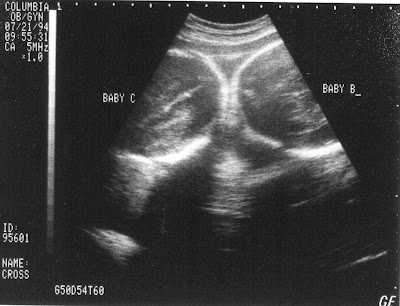

Can y'all indulge me for another year? Didn't I just post that our girls were turning 13 years old or something like that? Well, today, our precious identical triplet girls turn 18 years old!!! I can't believe they are 18. Where does the time go? I am sure today will be spent with many tears yet again--tears of happiness, excitement for them but sadness for me. Here they are at a time when we wondered what they would look like, would they be okay, how big would they be, were they girls or boys--